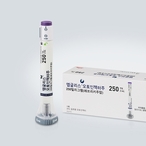

국제약품, 항혈전제 포트폴리오 확장…‘안티그렐정’ 출시

- 2026-04-08 08:51

- 김용발 기자